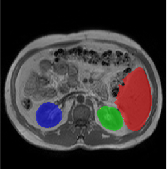

Table 2 presents an ablation study and compares SparseMamba-PCL with nine SOTA scribble-supervised methods across the three datasets. Out method achieves the highest Dice score across all the datasets, and the lowest (CHAOS) and second lowest (ACDC and MSCMRSeg) HD95 values, confirming its effectiveness in segmentation accuracy and boundary refinement. Baseline+SPOBE and Baseline+PCL improve upon the Baseline (SparseMamba), demonstrating the benefits of boundary-aware supervision and SAM-guided learning. Fig. 4 (l) compares the segmentation performance of SparseMamba-PCL with other scribble-supervised methods, showing smoother edges that precisely delineate object boundaries, unlike the jagged or blurred edges in other methods. The examples also demonstrate the consistent segmentation quality achieved by SparseMamba-PCL across ACDC, CHAOS, and MSCMRSeg, highlighting its adaptability across multiple medical domains. This adaptability and precise segmentation is crucial for accurate volumetric analysis and clinical decision-making, where even subtle boundary inaccuracies can lead to diagnostic errors. In summary, the SparseMamba-PCL architecture provides a consistent and robust improvement in segmentation metrics across diverse medical image datasets.

Refer to caption Refer to caption Refer to caption Refer to caption Refer to caption Refer to caption Refer to caption Refer to caption Refer to caption Refer to caption Refer to caption Refer to caption

(a) (b) (c) (d) (e) (f) (g) (h) (i) (j) (k) (l)

Figure 4: Qualitative comparison of weakly-supervised segmentation methods on ACDC, CHAOS, and MSCMRSeg datasets. (a) Input image, (b) ground truth, and segmentation results from (c) USTM [16], (d) Scribble2D5 [5], (e) CycleMix [26], (f) ShapePU [27], (g) S²ME [21], (h) ScribbleVC [12], (i) TDNet [30], (j) PacingPseudo [25], (k) Scribbleformer [13], and (l) SparseMamba-PCL are given.